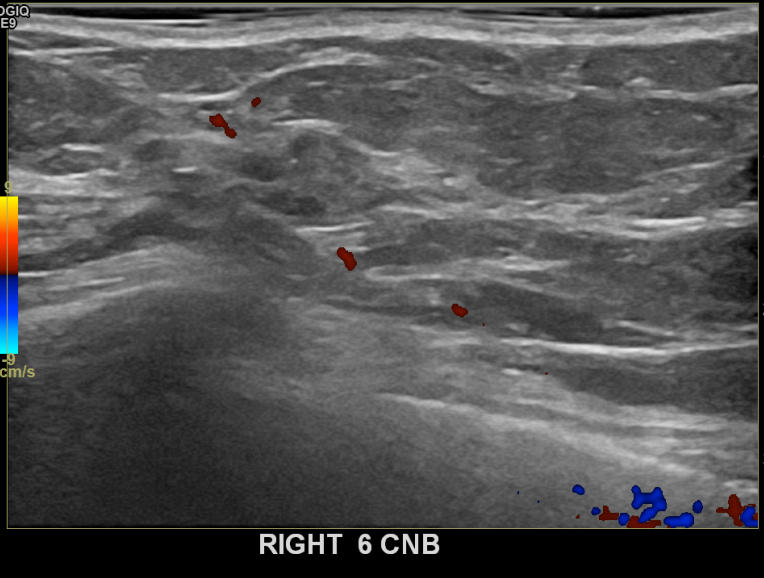

상기환자 본원에서 꾸준히 추적관찰하던 50대 여성분으로 새롭게 생겨난 혹 있어 우측유방멍울 조직검사시행후 유방암 진단되었습니다.